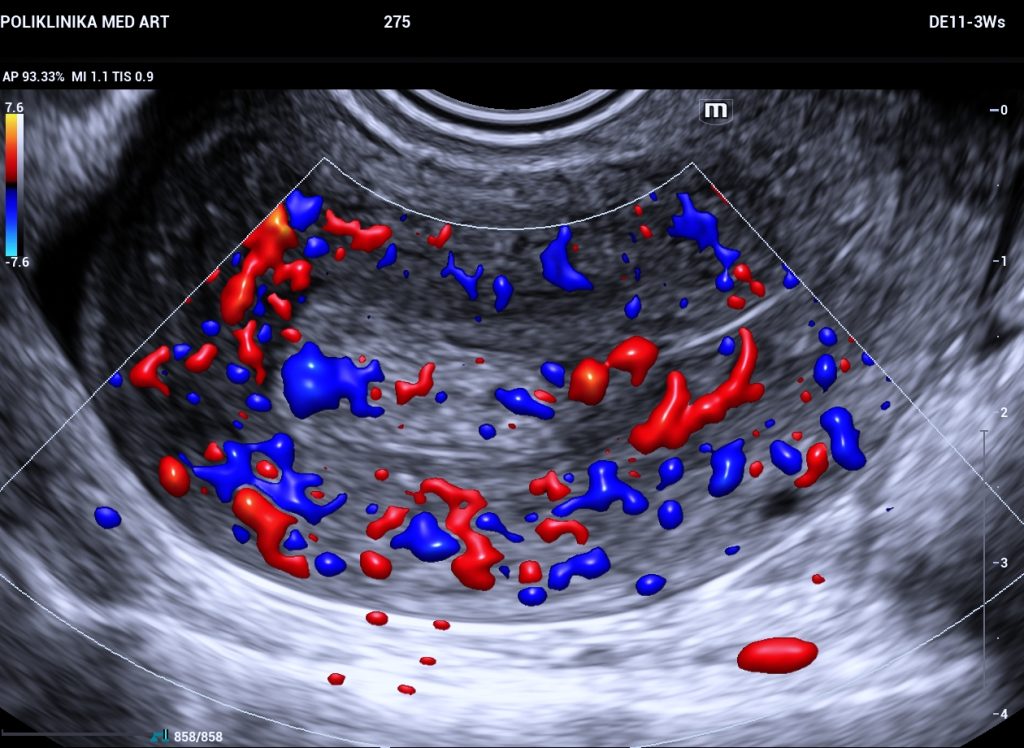

Razlika između dobroćudnog polipa i maligne tvorbe se može odrediti jedino patohistološkom analizom, što znači da je potrebno polip ukloniti i poslati patologu koji će odrediti o kakvoj vrsti promjene se radi. Ultrazvučnim pregledom se može postaviti sumnja na malignu promjenu ako je tvorba velika, nepravilnog izgleda, ima nepravilne rubove, obilnu prokrvljenost s više žila hranilica. No, ultrazvuk nije dovoljan za definitivnu dijagnozu radi li se o dobroćudnoj ili zloćudnoj tvorbi. Nije nužno kod svakog polipa ići na operaciju, može se planirati ultrazvučno praćenje ako tvorba ne izgleda sumnjivo.

| polip na maternici | pojačano menstrualno krvarenje i sukrvica unutar ciklusa | ovalna tvorba jasnih granica | jedna pravilna žila hranilica koja ulazi u polip | iste boje kao i sluznica maternice -bjelkaste boje | mekan, ali kompaktan i može se ukloniti u cijelosti |

| miom | pojačano menstrualno krvarenje i sukrvica unutar ciklusa | okruglasta tvorba jasnih granica | pravilan periferni protok oko mioma | tamniji od sluznice maternice, sjena iza mioma | tvrd i čvrst, može se ukloniti u cjelosti |

| karcinom | vrlo nepravilno, jače i učestalo krvarenje | nepravilna tvorba nejasnih granica prema okolnim strukturama | više nepravilnih krvnih žila koje ulaze u tvorbu, jaka prokrvljenost tvorbe | tkiva različite obojenosti unutar strukture, nema pravila | rasipa se prilikom otklanjanja, histeroskopija nije definitivna operacija |

Fotografija: Color Doppler prikaz polipa u maternici